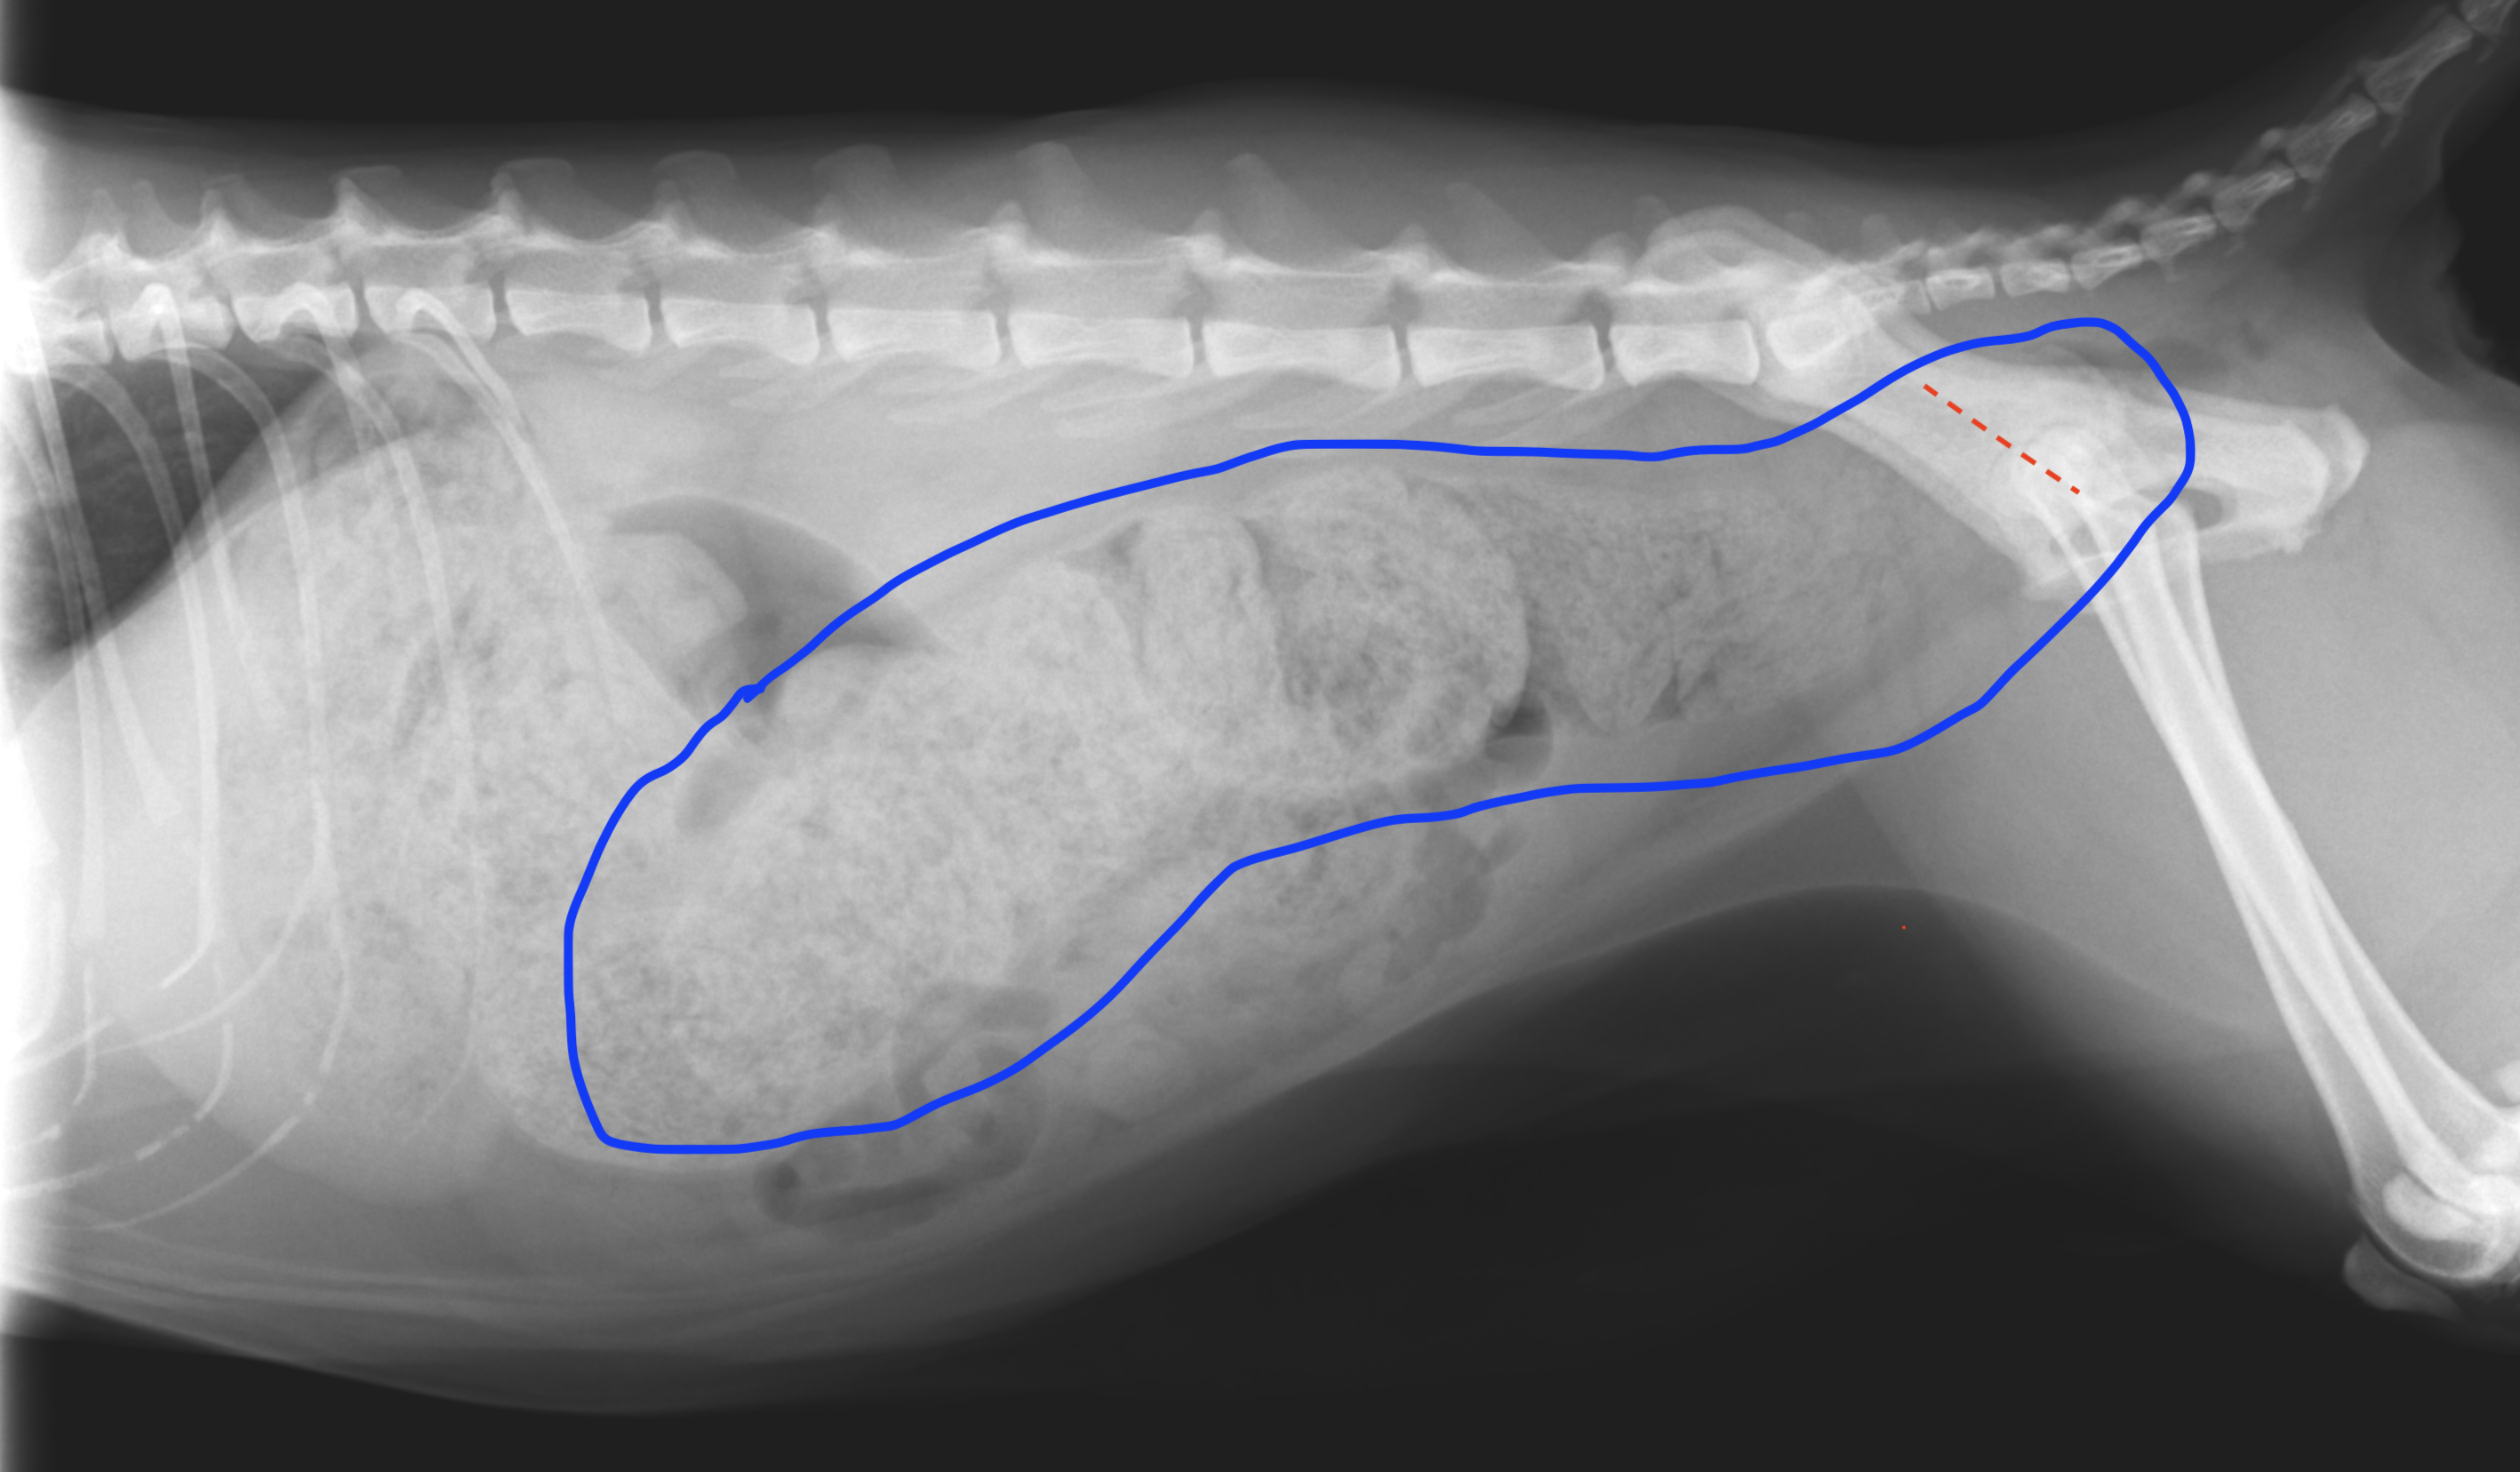

重度便秘の猫のレントゲン写真です。左側が頭方向で撮影しています。青線で囲まれた白い部分が結腸に溜まった便です。白が濃い程硬く出づらい便の可能性が高く、赤点線の骨盤の狭い部分が通れなくなっています。